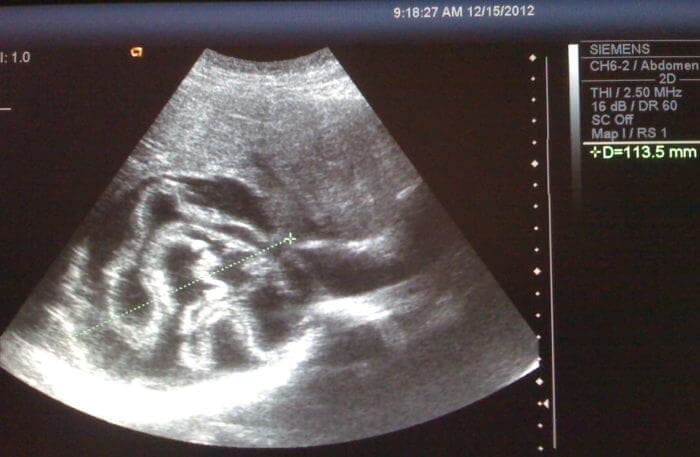

Po príchode do nemocnice nám dal doktor hroznú diagnózu - parazitická infekcia. Takmer 70% tela môjho manžela bolo napadnutého parazitmi, kdekoľvek. Celkom som tomu nerozumela, môj dom je čistý, má dezinfekčný papier, jedlo varím pozorne a čisto. Nikdy by som nečakala, že tieto mierne príznaky boli znakom parazitickej infekcie.